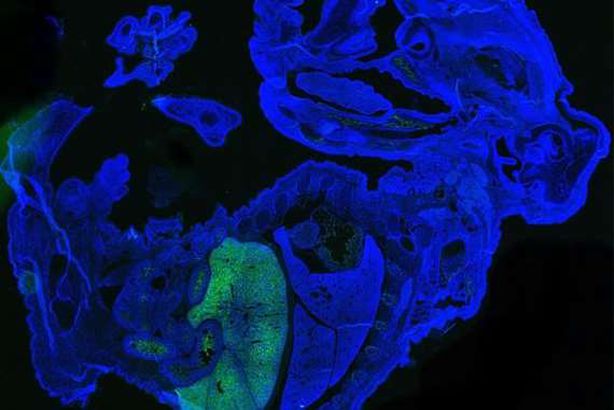

نجح العلماء في تطوير هجين بشري حيواني من خلال مزج الخلايا البشرية والفئران، في واقعة هي الأولى من نوعها لاحتوائه على نسبة خلايا بشرية هي الأكبر التي تسجل في هذا المضمار.

وقام الفريق بحقن ما بين 10 و 12 دفعة من هذه الخلايا الجذعية البشرية الساذجة في أجنة الفئران وتركوها لتتطور لمدة 17 يومًا.

تحتوي الأجنة الناتجة على ما بين 0.1 إلى أربعة بالمائة من إجمالي خلاياها من الخلايا الجذعية البشرية.

وكانت الخلايا الجذعية البشرية أكثر وفرة في خلايا الدم الحمراء المتداولة في الجنين، وكانت موجودة أيضًا في أنسجة الكبد والقلب وخلايا العين وحتى الدماغ.